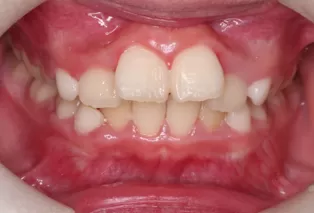

Patient: Female, 11 years old

Conditions: Deep overjet, upper anterior teeth protrusion

Treatment Device: K3

Intraoral photos